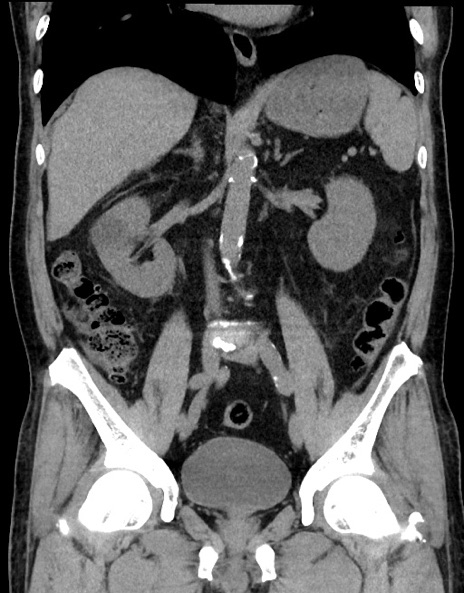

症例15(冠状断像)

【症例】70歳代男性

【主訴】腹痛

【現病歴】今朝から腹痛あり。全体的に痛い。特に左上の方。排ガスが今日はない。冷や汗が出る。

【既往歴】直腸癌術後

【身体所見】左側腹部〜上腹部に圧痛あり。腹膜刺激症状明らかなではない。軽度反跳痛。左下腹部に術後瘢痕あり。

【データ】WBC 7700、CRP 0.02

横断像